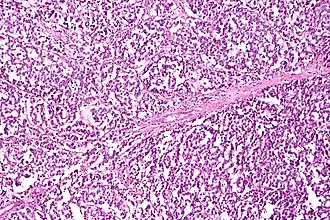

| Micrograph of a mucinous ovarian carcinoma stained by H&E | |

Mucinous tumors include mucinous adenocarcinoma and mucinous cystadenocarcinoma.[29]

Mucinous adenocarcinoma

Mucinous adenocarcinomas make up 5–10% of epithelial ovarian cancers. Histologically, they are similar to intestinal or cervical adenocarcinomas and are often actually metastases of appendiceal or colon cancers. Advanced mucinous adenocarcinomas have a poor prognosis, generally worse than serous tumors, and are often resistant to platinum chemotherapy, though they are rare.[29]